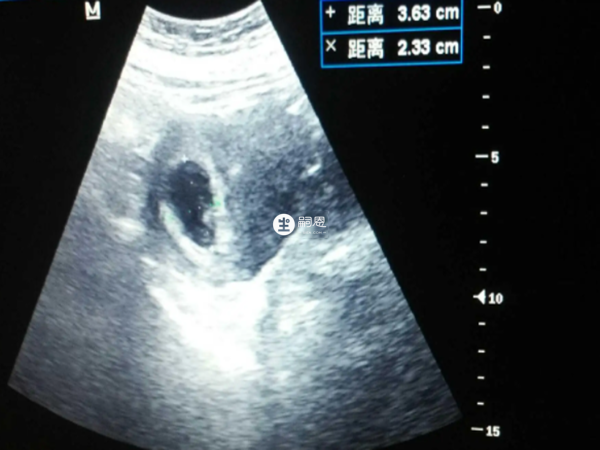

最近在網路上有寶媽分享稱超聲檢查後,發現孕囊偏左側有大夫說是生男孩,很多人都說這個說法是很準的,在懷孕期間通過孕囊位置能否看出孩子的性別是有爭議的,有興趣的可以瞭解一下具體情況。

9、孕囊偏左側大夫說是男孩